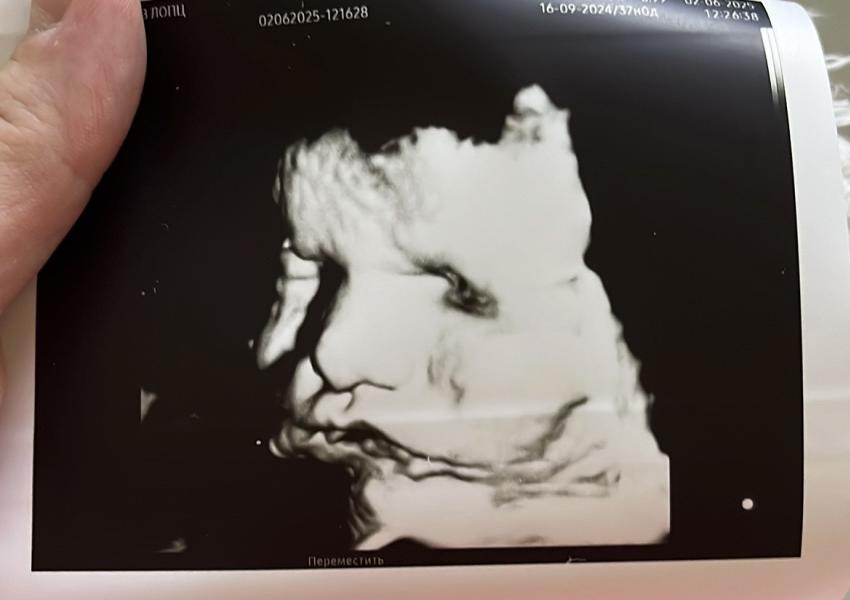

Госпитализировались мы. По узи вес уже 4400🫣, титры 1:2048, по доплеру ухудшения кровотока (1,5МоМ), неделю назад МоМ был 1,2. Ждем скорейшего родоразрешения🤞🏻🤞🏻🤞🏻. Сыну уже тесно, щеки наел знатно.